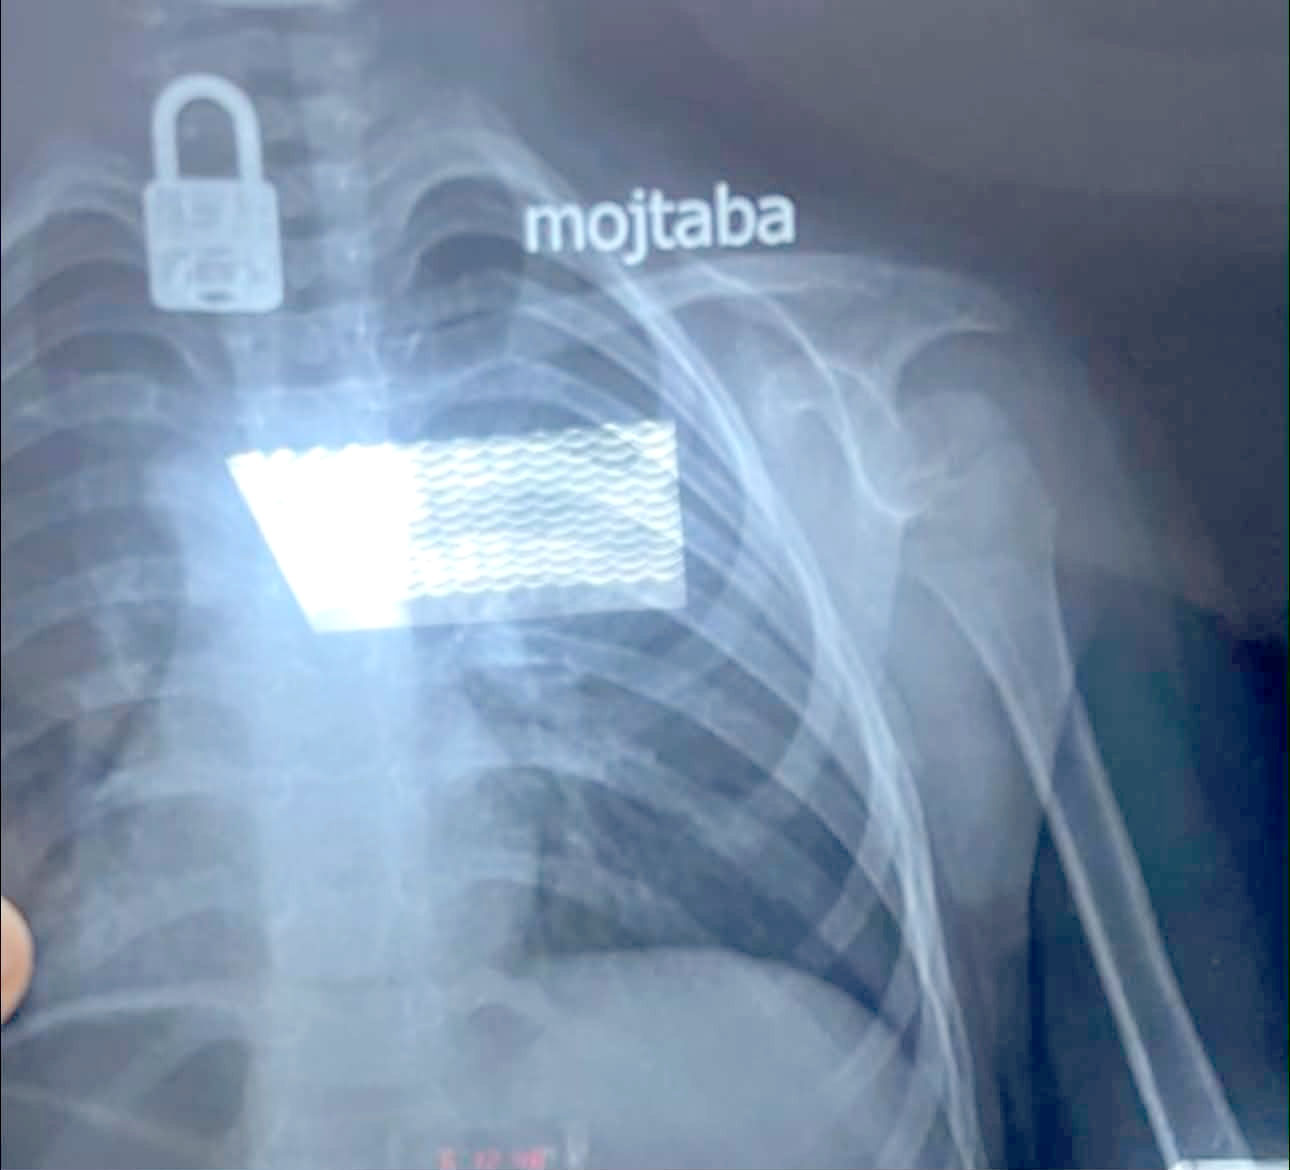

نجح فريق طبي بمستشفى الزهراء التعليمي التابع لدائرة صحة النجف، في استخراج قفل من جسم طفل يبلغ من العمر أربع سنوات. وقال بيان تلقته (الزمان) أمس إن (قسم جراحة الأطفال استقبل حالة طارئة لطفل يبلغ من العمر أربع سنوات بعد ابتلاعه جسماً غريباً). وأضاف إنه (بعد إجراء فحص بالأشعة السينية تبين وجود قفل داخل جسم الطفل، وعلى إثر ذلك تم التنسيق مع مدينة الصدر الطبية وتحديداً قسم جراحة القلب والأوعية الدموية لاستخراجه). وتابع البيان إنه (تمت العملية بنجاح عبر الناظور، وإن الطفل يتمتع حالياً بحالة صحية جيدة). فيما أكد مصدر طبي، وفاة طفلة حديثة الولادة وإدخال والدتها إلى العناية المركزة، إثر خطأ في نقل فصيلة الدم داخل أحد مستشفيات ذي قار. وقال المصدر أمس إن (امرأة في العشرينات من عمرها أُدخلت إلى وحدة الولادة في مستشفى الحبوبي وسط مدينة الناصرية، وكانت حالتها الصحية تستدعي نقل دم من فصيلة، إلا إنه تم تزويدها بدم من فصيلة أخرى). مؤكداً إن (المريضة وضعت طفلتها، التي توفيت بعد نحو ساعة من الولادة). مبيناً إن (الأم لم تتوفَ نتيجة تلقيها سابقاً علاجات خاصة بحالات عدم توافق فصائل الدم، لكنها تعرضت لمضاعفات خطيرة أدت إلى تدهور حالتها الصحية). وأشار إلى إن (الأم نُقلت لاحقاً إلى المستشفى التركي وأُدخلت وحدة الإنعاش، بعد تعرض بعض أعضاء جسدها لمضاعفات حادة نتيجة نقل الدم غير المطابق). وشدد على القول إن (الجهات التحقيقية باشرت في فتح تحقيق موسع للوقوف على ملابسات الحادث وتحديد المقصرين).